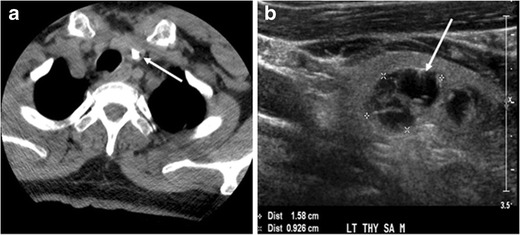

- Nodules thyroïdiens: souvent bénins, mais certains peuvent indiquer une croissance cellulaire anormale.

Caractéristiques d’imagerie : des bordures irrégulières ou des caractéristiques internes spécifiques observées sur des échographies, des tomodensitogrammes ou des IRM peuvent suggérer un potentiel de malignité.

Résultats de la biopsie : une biopsie est la méthode la plus fiable pour déterminer si un nodule est bénin ou malin en examinant un échantillon de tissu.